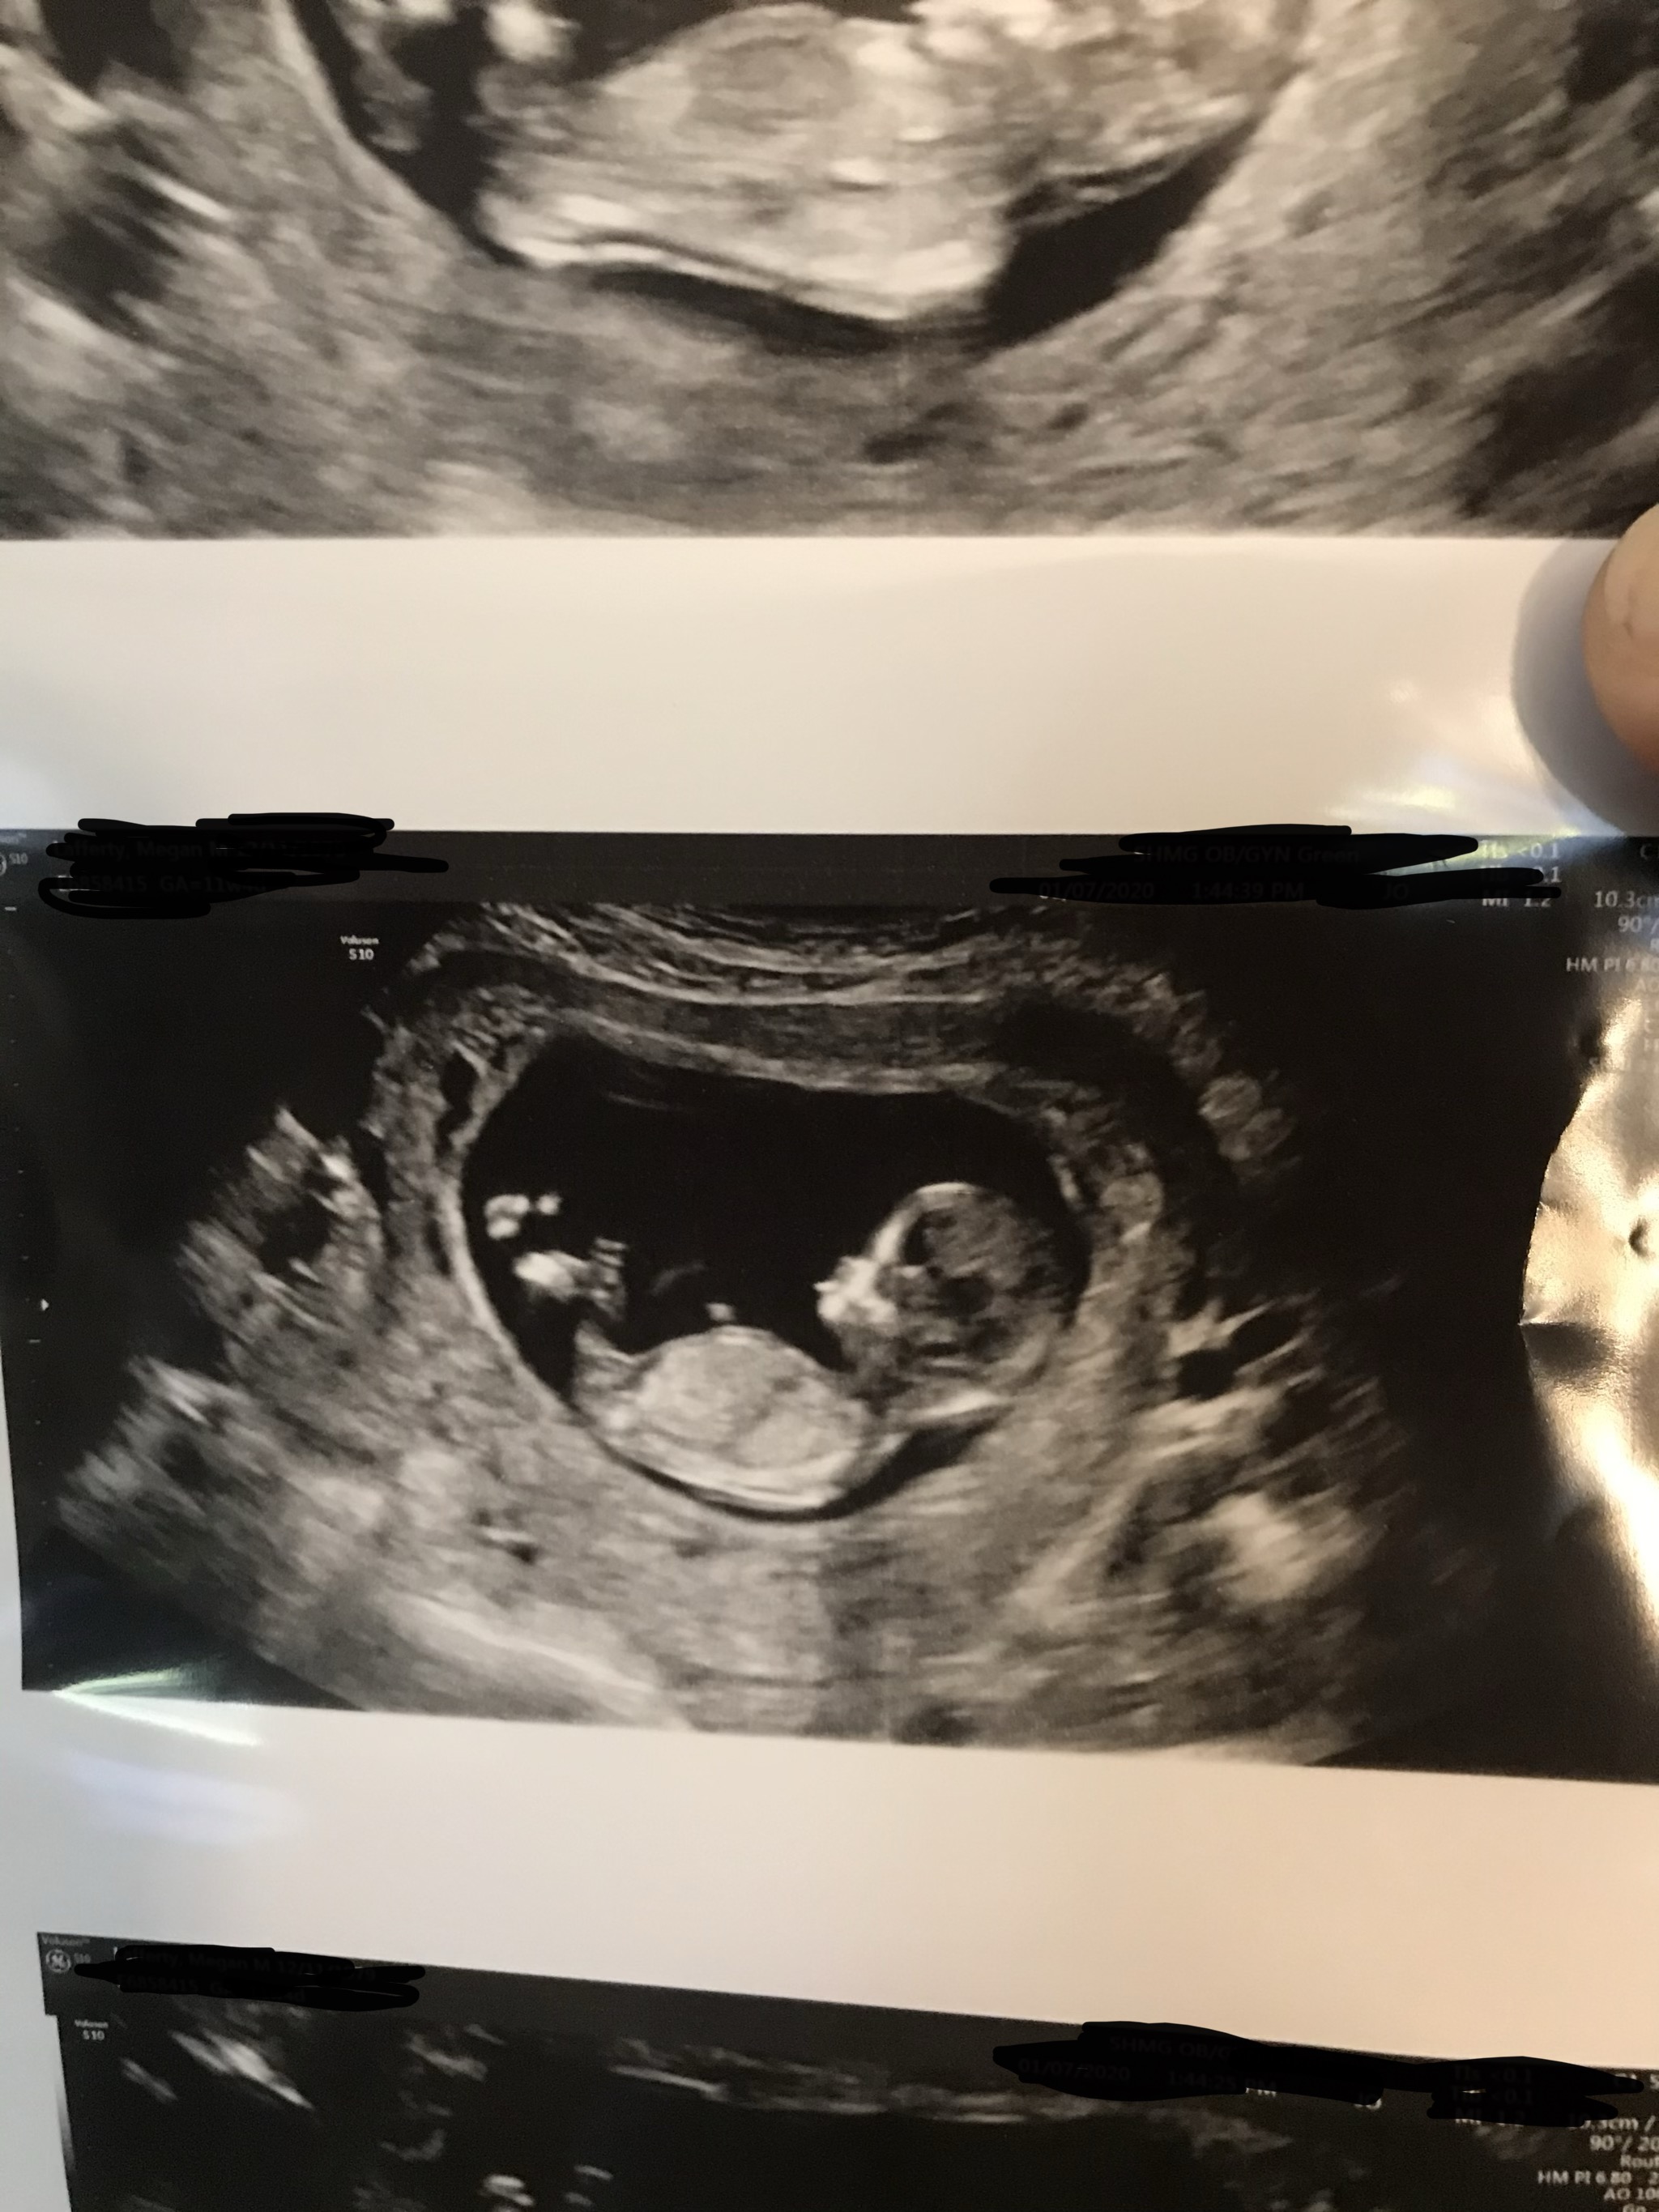

Lemme know what you think. Attachment 42283

Unfortunately it's too early to guess just yet. Towards the end of the 12th week it becomes more reliable.